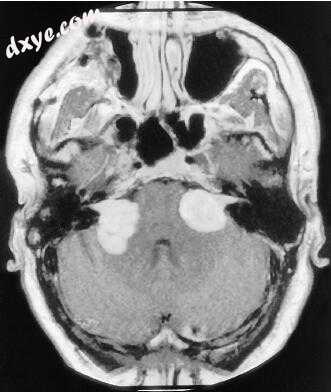

5.jpg

图-5. 钆增强的磁共振图像显示中等大小的前庭神经鞘瘤。